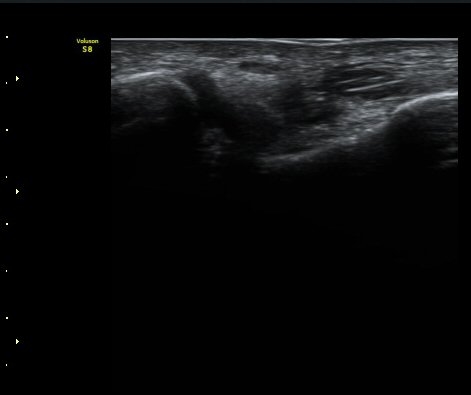

ºñ°ñÁ¾°ñÀδë Á¾´Ü¸é°Ë»ç¿¡¼­ ƯÀÌ ¼Ò°ßÀ» º¸ÀÌÁö ¾Ê´Â´Ù(±×¸² 5).

±×¸²5) ºñ°ñÁ¾°ñÀδë Á¾´Ü¸é°Ë»ç